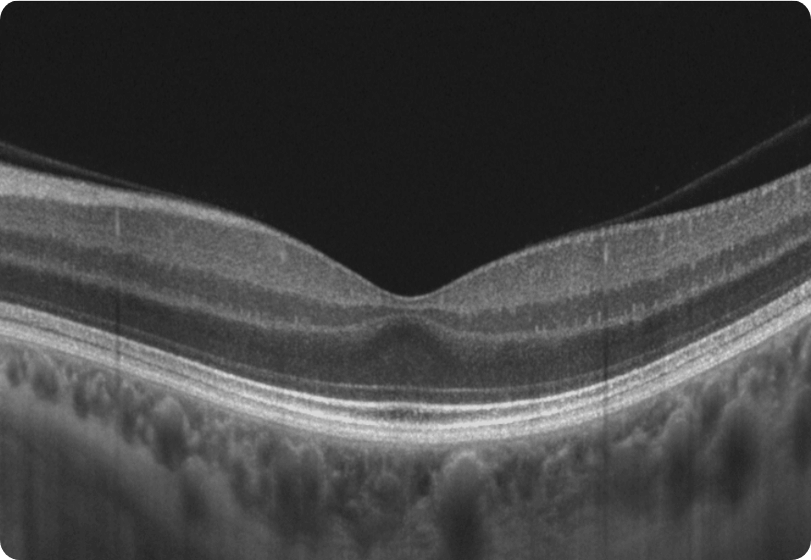

With a unique combination of super-fast scanning at 130,000 scans per second and ultra-high 3μm resolution, this powerful device takes precision, accuracy, and detection of even the finest lesions to a whole new level. The REVO HR is an all-in-one device you can use in a number of ways such as a full colour fundus camera or as a combo, providing simultaneous OCT and fundus images for high quality OCT imaging, including OCT-A.

Wide Retina and Anterior Scans

A.I. DENOISE

An advanced artificial intelligence (AI) algorithm removes noise from the tomogram for the highest image quality.